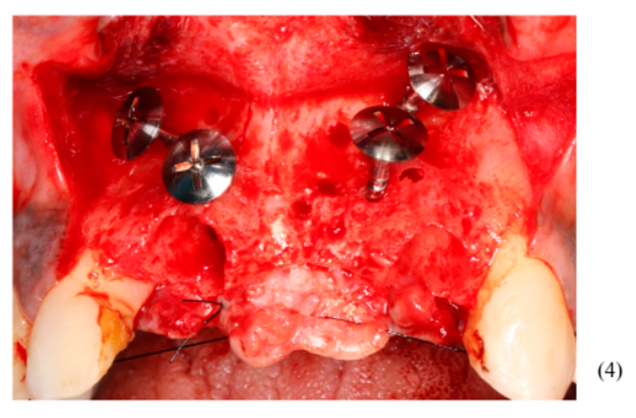

Figuras 3,4,5,6,7 e 8 – Sequência do primeiro ato cirúrgico, onde podemos observar (imagem 3) a incisão do tipo Newmann modificada para ampla visualização do campo operatório e as extrações dentárias. Podemos observar também a descorticalização do processo alveolar e a instalação dos parafusos tipo tenda Implacil De Bortoli de 10 mm, respeitando a distância de pelo menos 2 mm entre cabeças (imagem 4). Foram colocados dois gramas de biomaterial Bio-Oss Geistlich, preenchendo toda cavidade e alvéolos até a delimitação da cabeça dos parafusos (imagens 5 e 6). Antes do fechamento completo da ferida cirúrgica, colocamos membranas de PRF para auxílio na reparação tecidual e proteção do material de enxerto (imagem 7). Para fechamento da ferida cirúrgica, usamos fio do tipo Cytoplast, fornecido pela Implacil De Bortoli. É de extrema importância sua utilização, pois apresenta excelente elasticidade, acompanhando edema cirúrgico pós-operatório, o que diminui o risco de deiscência no pós-operatório.